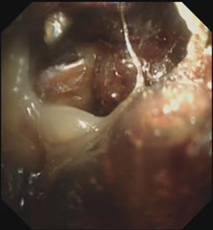

时间紧迫,每一秒都关乎生命,患者立即被送到内镜室,支气管镜检查的结果令人触目惊心:患者的总气管被痰痂、血痂、痰栓等物几乎完全堵死,仅残留一丝细小的通气通道,那是生命最后的脆弱纽带!

在紧张且充满紧迫感的抢救氛围中,呼吸介入团队成员默契配合,在支气管镜下使用异物钳夹取、超低温冷冻等方法清除异物。

随着每一次精准夹取和冷冻操作,顽固的异物被一点点从狭窄的气道内剥离出来,堆积在一旁的痰痂、血痂和痰栓逐渐增多,堆积起来的长度居然达到了惊人的18厘米。

当最后一块异物被取出,患者的气管终于露出了原来的“庐山真面目”: